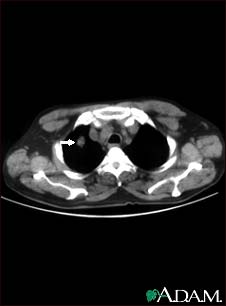

Pulmonary nodule, solitary - CT scan

This CT scan shows a single lesion (pulmonary nodule) in the left lung. This nodule is seen as the light circle in the upper portion of the dark area on the left side of the picture. A normal lung would look completely black in a CT scan.